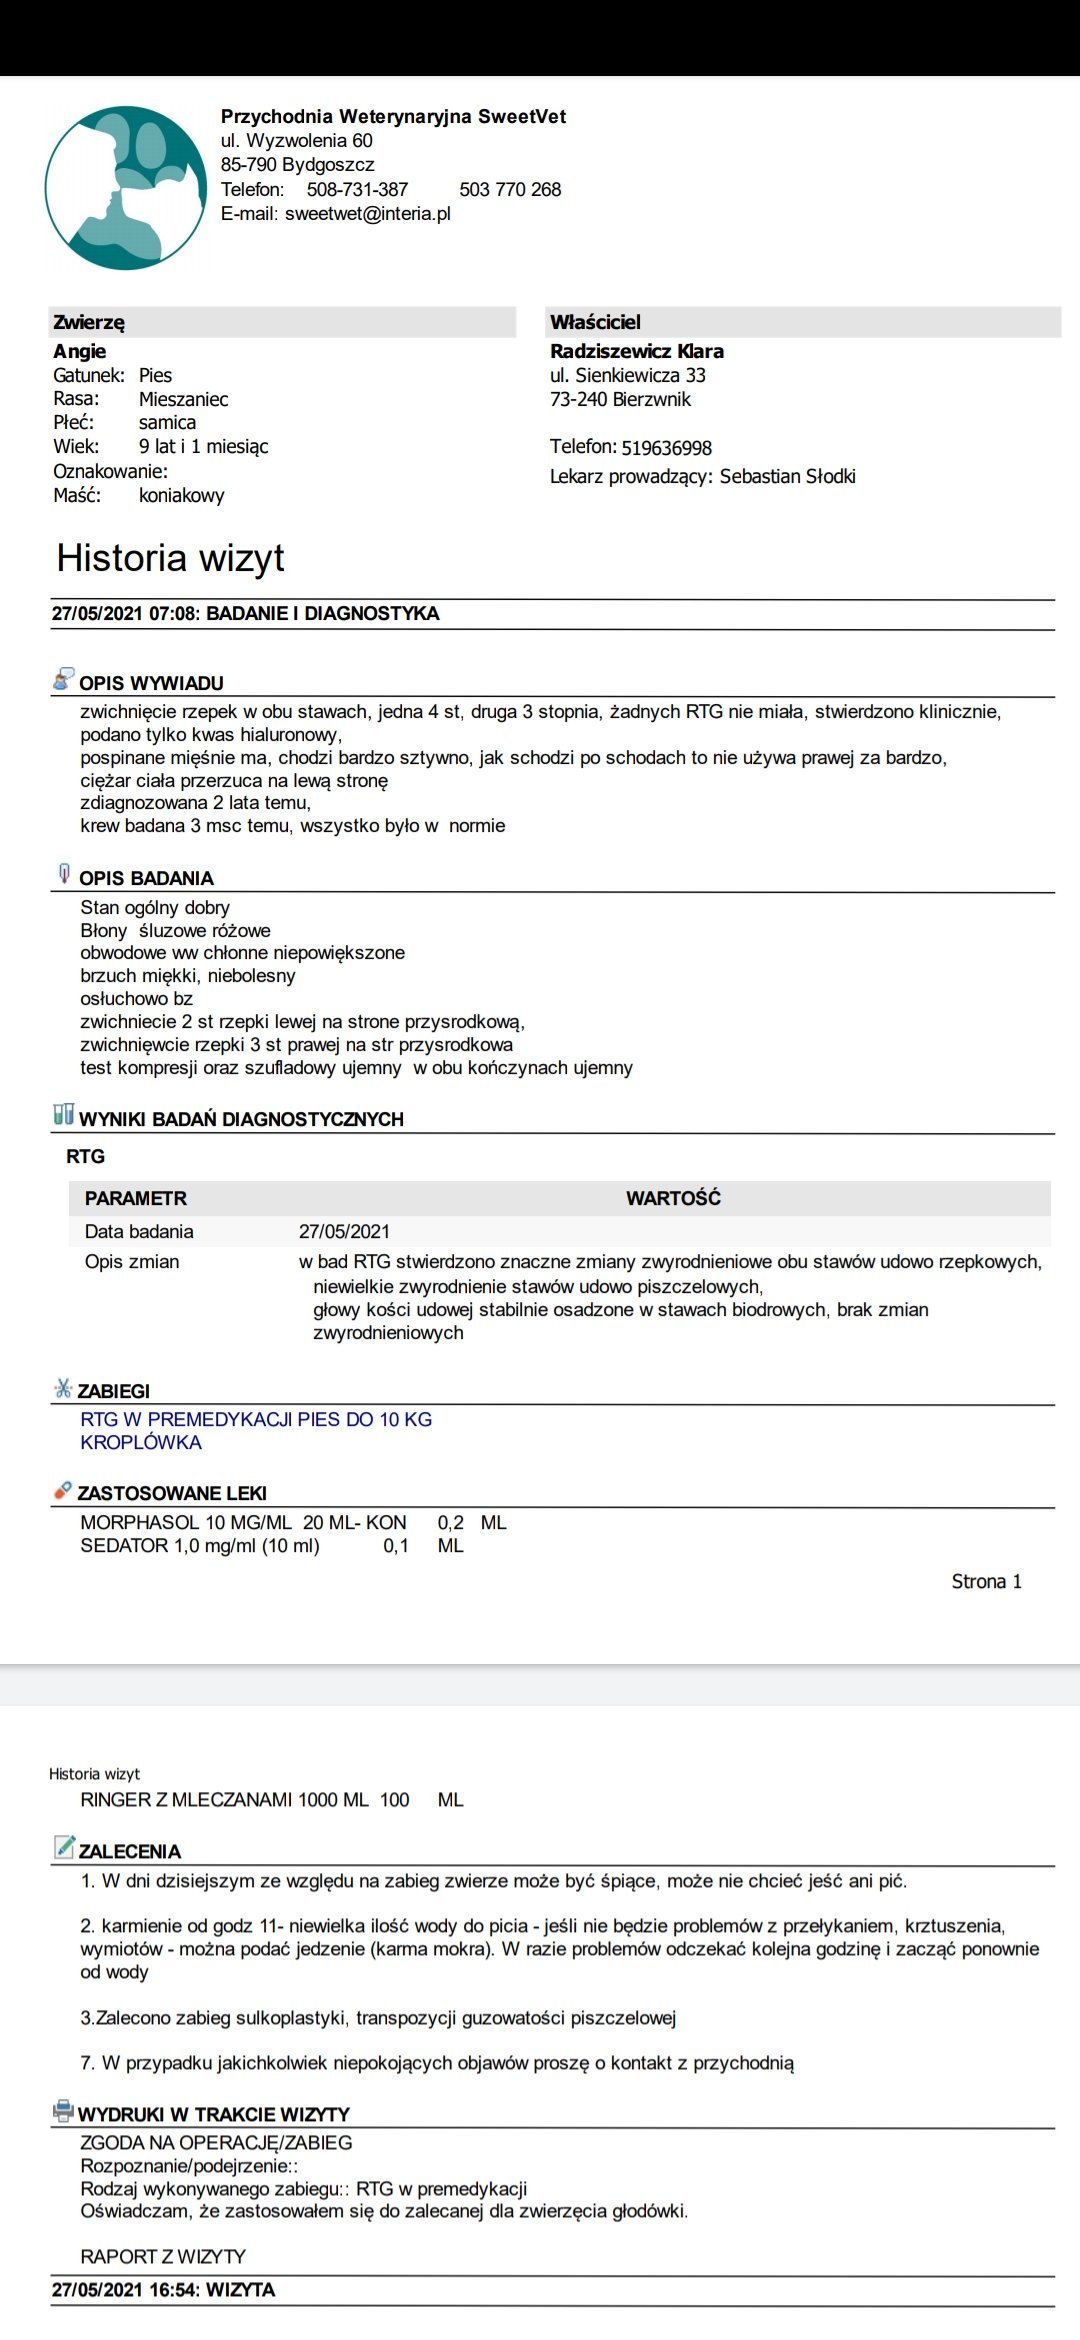

Dwa lata temu Angie wróciła ze spaceru z tatą kulejąc. Oczywiście niezwłocznie pojechałam z nią do weterynarza. Lekarz zbadał ją palpacyjnie i stwierdził zwichnięcie rzepek w obu stawach 2-ego i 3-ego stopnia. Dowiedziałam się, że jedynym wyjściem z tej sytuacji jest zabieg kosztujący dobre 3000zł, których oczywiście w wieku 19 lat absolutnie nie miałam, a moich rodziców nie było na to stać.

Rok później zmieniłam lecznicę, w której przyjmuje ortopeda. Angie nie używała prawej tylniej łapki schodząc po schodach, a że ciągle wyskakiwały jej rzepki, zaczęła usztywniać łapki, by się przed tym uchronić. Postanowiłam jeszcze raz spróbować, być może ten lekarz postawi inną diagnozę, znajdzie inne rozwiązanie. Ponownie przy jedynie badaniu palpacyjnym (bez zdjęć RTG, ponieważ lekarz twierdził, że nie są potrzebne w tym przypadku) stwierdzono zwichnięcie rzepek w obu stawach 3-ego i 3/4-ego stopnia. Wtedy wiedziałam, że jeśli jest możliwość wykonania zabiegu, to stanę na głowie żeby uratować swojego psa od bólu. Weterynarz stwierdził jednak, że zabieg w tym wieku może być ryzykowny (mimo idealnych wyników krwi), a nie przyniesie spodziewanych rezultatów, więc 3 miesiące temu zdecydowałam się na zabieg ostrzykiwania stawów kolanowych kwasem hialuronowym, żeby choć trochę zwiększyć komfort życia i poruszania się Angie.

Na nasze szczęście wraz z początkiem maja dostaliśmy możliwość odbywania raz w tygodniu zajęć praktycznych na uczelni w Bydgoszczy. Jako, że mieliśmy opcję przyprowadzić na zajęcia własne zwierzęta i na nich ćwiczyć, zabrałam ze sobą moją Angie. Już na pierwszych zajęciach sunia pokazała dużą bolesność mięśni grzbietu. Tydzień później przy próbach masażu kończyn miednicznych psinka zareagowała agresywnie, od razu dała znać, że nie chce być tam dotykana. Na naszej uczelni przyjmuje fizjoterapeuta zwierząt, więc postanowiłam zaprowadzić tam swojego psa. Okazało się, że mięśnie tylnich łap i kręgosłupa są tak pospinane, że wywołują bardzo dużą bolesność. Przez odciążanie prawej (gorszej) łapki, mięśnie lewej są ciągle spięte, obolałe, przeciążone. Zaczęłyśmy działać przeciwbólowo i rozluźniająco poprzez laseroterapię, ultradźwięki i magnetoterapię. Pani zoofizjoterapeutka poleciła mi jeszcze zrobić dokładne zdjęcia RTG w jednej z bydgoskich klinik (ponieważ bez nich ciężko było wykluczyć bądź potwierdzić wskazania do zabiegu).

Nie zamierzałam się poddać i jeszcze w tym samym tygodniu pojechałam do kliniki Sweetvet na zdjęcia i konsultacje. Okazało się, że mimo tak dużej przestrzeni czasowej od wstępnej diagnozy stawy kolanowe Angie nie są w tragicznym stanie: lewa rzepka-zwichnięcie 2-ego stopnia, prawa- 3-ego. Zdjęcia RTG wykazały zwyrodnienia rzepki i głowy kości udowej w obu kończynach. Bez zabiegu sulkoplastyki i transpozycji guzowatości kości piszczelowej pogłębiające się z czasem zwyrodnienia doprowadzą do zerwania więzadeł. Doktor potwierdził, że Angie jako zdrowy pies, z dobrymi wynikami jak najbardziej nadaje się do operowania, tym bardziej, że teraz jesteśmy w stanie kolosalnie zmienić jej komfort życia.